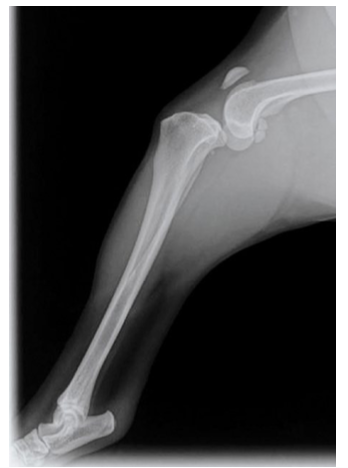

What is this?

deranged stifle (luxation of stifle joint due to multiple ligamentous injuries)